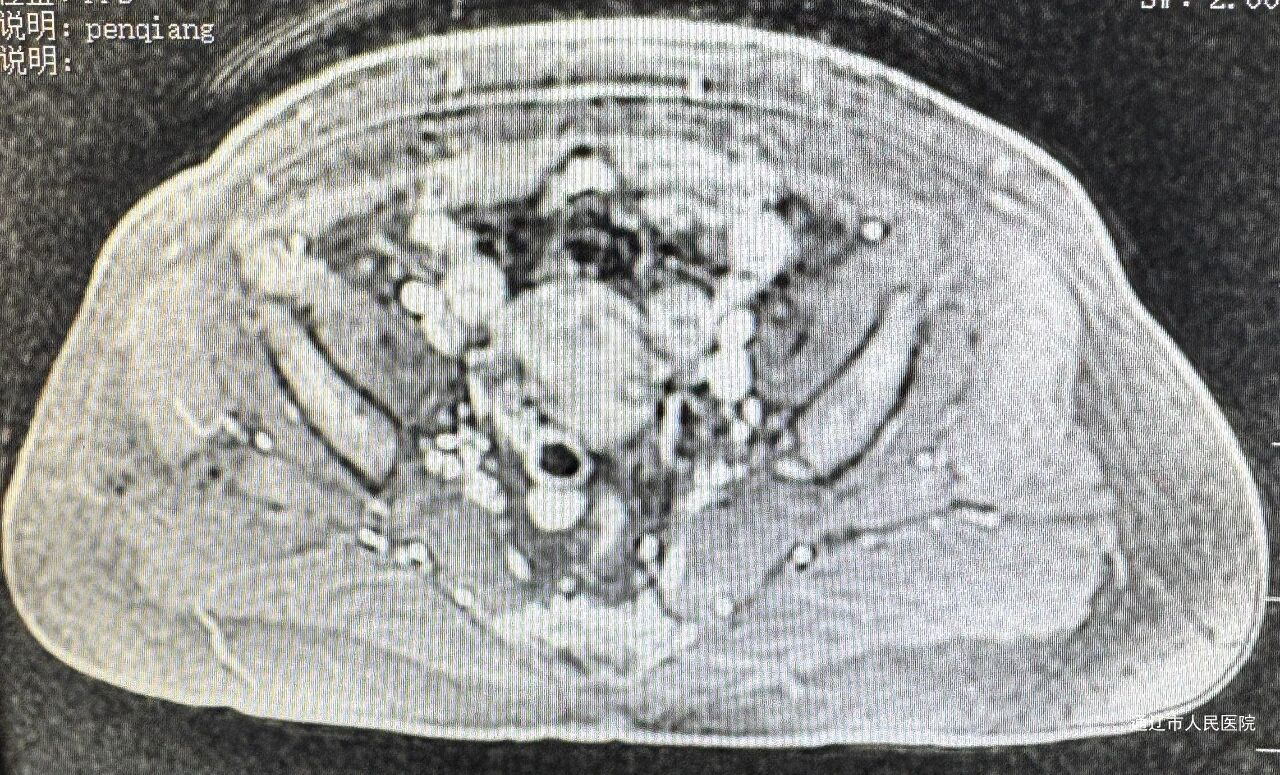

该患者年仅45岁,确诊时肿瘤病灶直径超过4cm,直接手术难度大、风险高。科室以副主任医师白鹏来为主导,结合患者年龄、身体状况及需求,制定个体化方案:先为患者进行2次术前辅助化疗,成功将病灶缩小至2.5cm,为实施腹腔镜宫颈癌根治术创造有利条件。

手术实施中,团队直面三大核心挑战:肿瘤体积大易致解剖结构偏移;需彻底清扫淋巴结的同时保护输尿管、血管及神经;需严格遵循无瘤原则防止术中扩散。为此,团队术前通过三维重建精准规划手术路径,术中借助腹腔镜放大视野清晰显露深层组织,以精细解剖技术逐层分离、完整切除肿瘤,同步完成淋巴结清扫与神经保护,实现根治性与安全性的平衡。